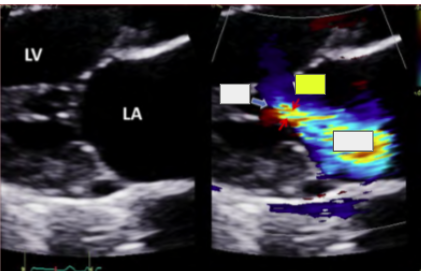

CFD

turbulent systolic flow. use mult views to avoid missing small/eccentric jets

most popular method to evaluate MR

CFD (BP and CFD gain affect jet size)

Severity Scale uses

Regurgitant jet area/LA area, CWD spectral strength/shape and PWD mapping

MR jet is just past the MV leaflets

MR jet is 1/3 the way into the LA

MR jet is 1/2 the way into the LA

MR jet is in the mid to back wall of the LA

vena contracta

VC >7 cm is severe MR

LV dilation jet

LV dilation has a central jet

ischemic MR jet

ischemic MR has an eccentric posterior directed jet

MVP jet

anterior jet is PMVL MVP and posterior jet is AMVL MVP